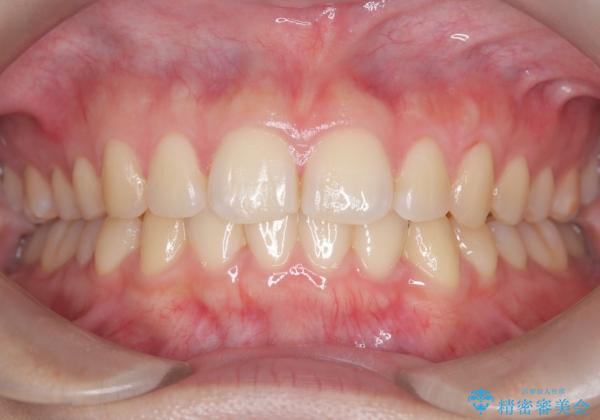

マウスピース矯正で前歯のガタツキを改善! 短期間で治療完了

- 治療期間

- 1年3ヶ月

- 治療計画